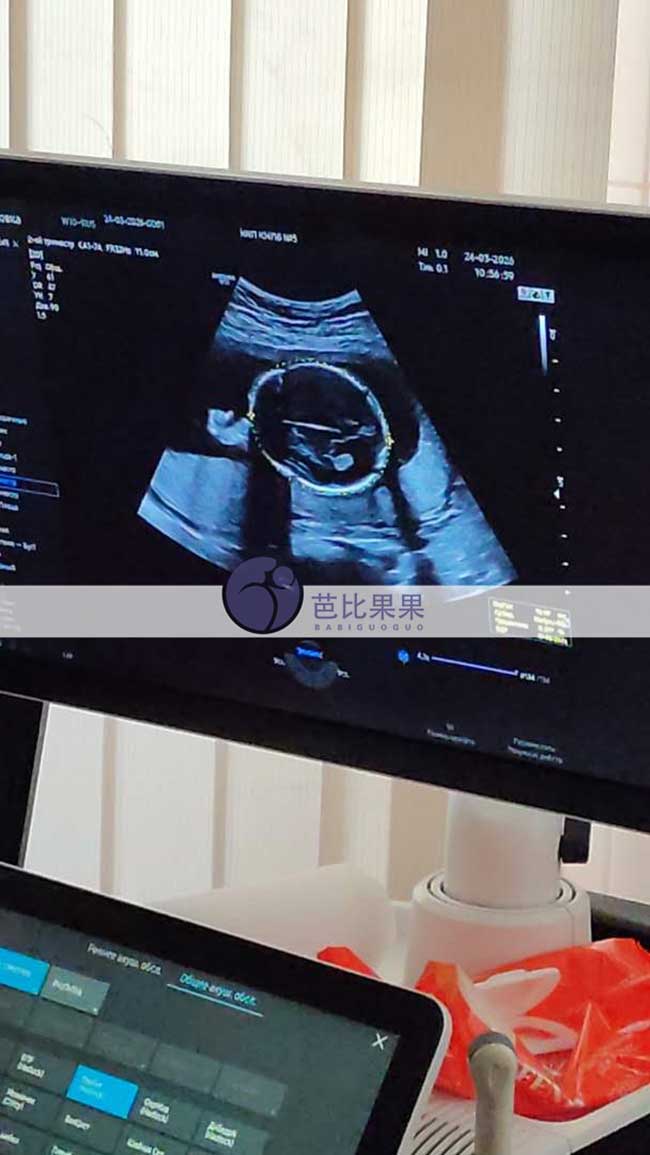

汪女士夫妇到乌克兰匹配的试管妈妈做产检B超结果出炉,胎儿发育健康顺利,期待小天使平安到来

汪女士夫妇到乌克兰匹配的试管妈妈做产检B超结果出炉